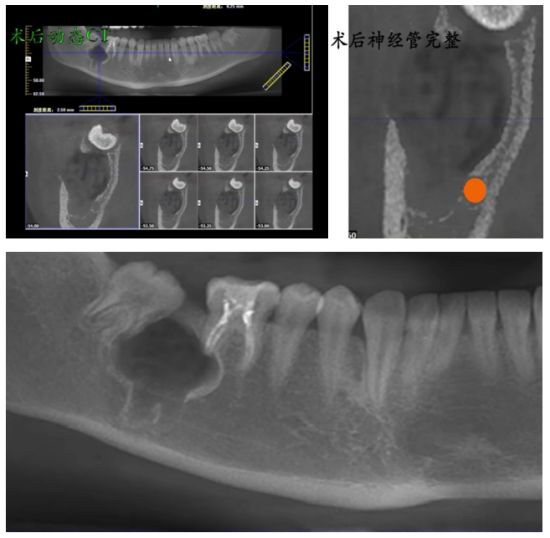

手术团队首先精心设计并切开角形牙龈黏膜瓣,微创地将其翻起,充分显露深部术区。依据术前锥形束CT(CBCT)提供的三维影像数据,团队在牙槽嵴顶下方约8毫米处精准定位,成功开窗,终于找到了“深藏不露”的47牙及其伴随的囊肿组织。随后,在清晰视野下,手术团队完整剥离并摘除了囊肿,确保无残留。针对拔牙难点,团队采用高速涡轮钻分牙技术,将患牙科学分割后逐一取出,并于术区外进行拼对,确认牙体完整拔除。操作尾声,团队对周围牙龈组织做了精细修整,填入胶原蛋白以促进愈合,最后严密对位缝合切口。整个过程流畅精准,最大程度保留了健康组织,为后续修复创造了良好条件。

术后进行抗炎对症治疗,十天后拆线,确保创口良好愈合。

未来治疗规划:正畸治疗恢复牙列完整

计划半年后开始正畸治疗,将48牙牵引至47牙的位置,恢复完整的牙列和功能。